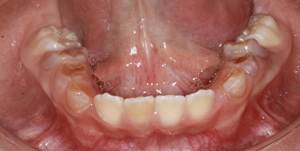

Figura 5. Arco superior en forma ovalada Figura

6. El arco inferior cuadrado

Figura 12. Análisis de los modelos de estudio.

Se puede determinar un arco inferior en forma cuadrada

Figura 13. Análisis de los modelos de estudio.

Un arco superior ligeramente en forma de V.